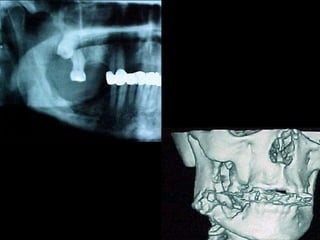

Diagnóstico diferencial

Schwannoma del trigémino, en el cuerpo o en cualquiera de

las ramas.

Los bloqueos de nervios con técnicas inadecuadas pueden determinar

Schwannomas o neurilemomas